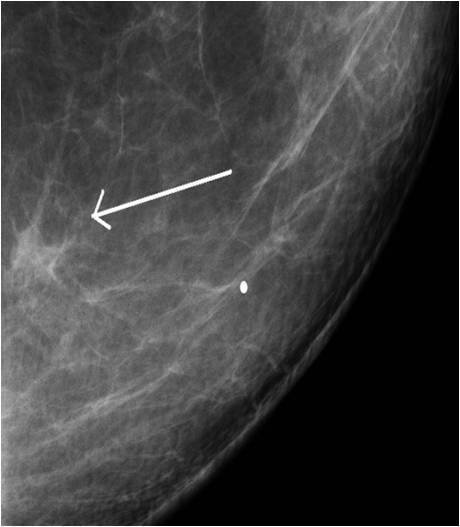

Image

Picture 2.